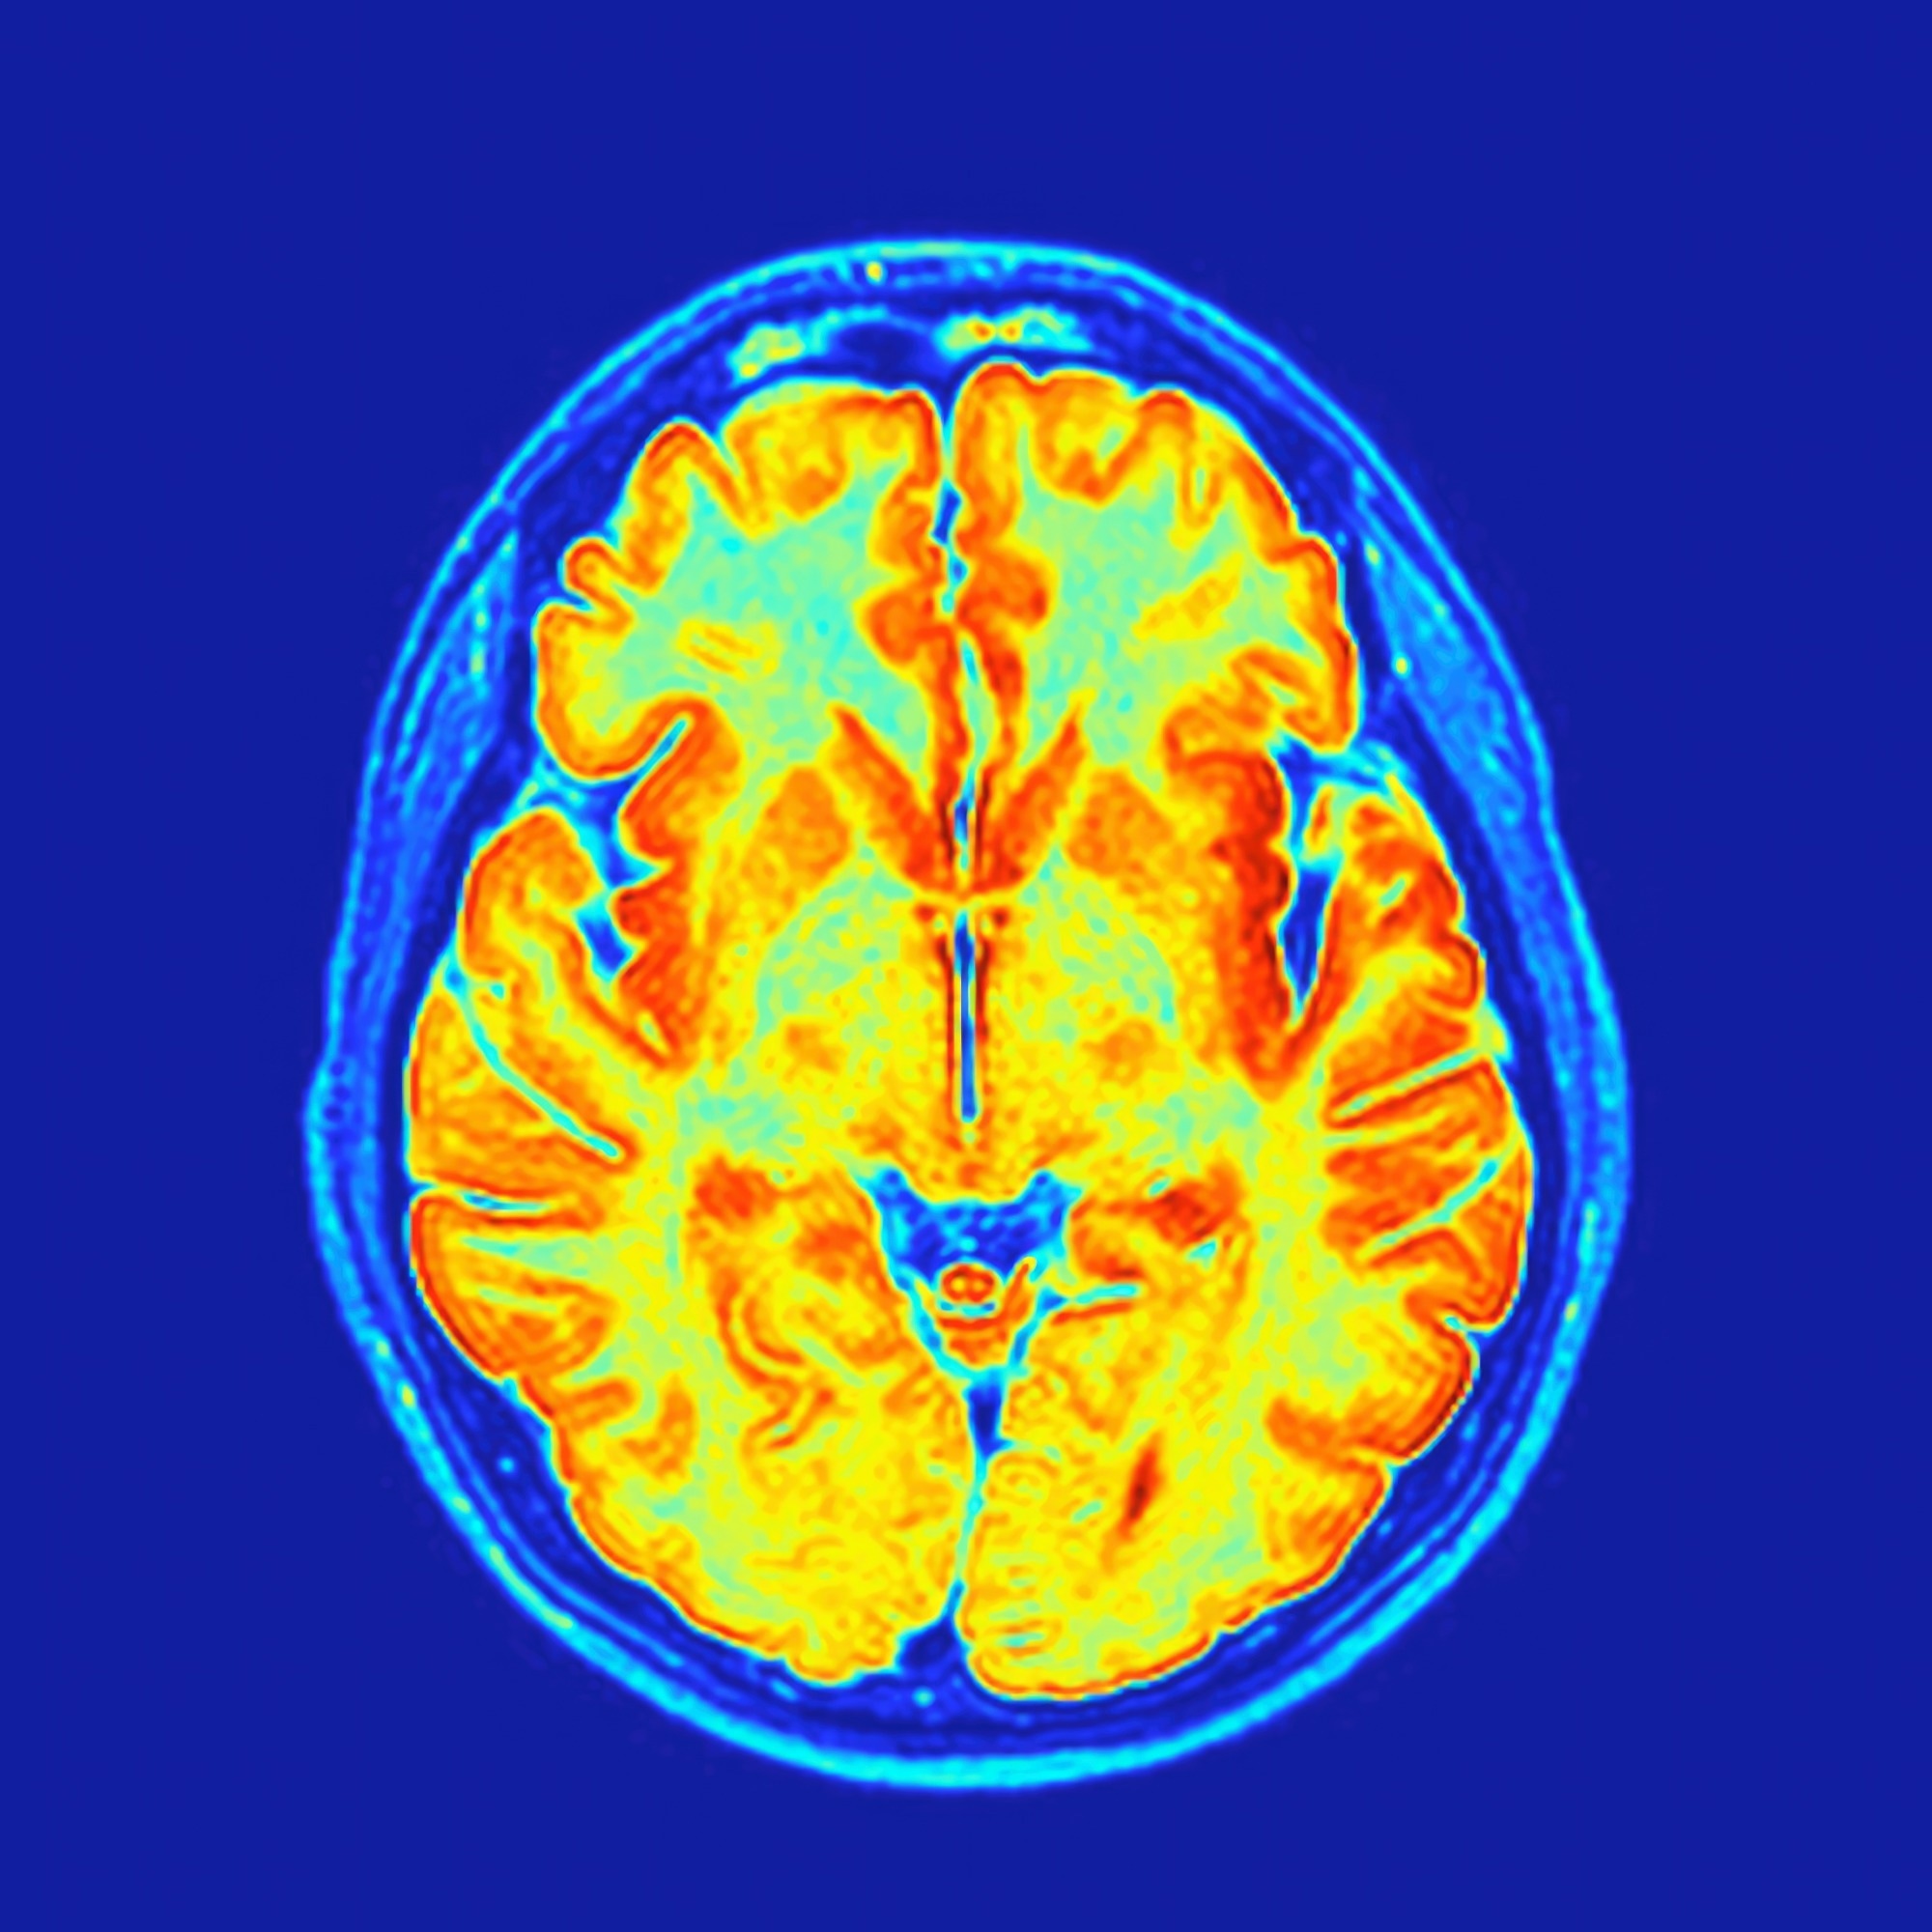

סריקות מוח חדשות בשדה גבוה במיוחד חושפות מפות גוף נסתרות בתוך מערכת הראייה, המראות כיצד המוח שוזר ראייה ומגע יחד